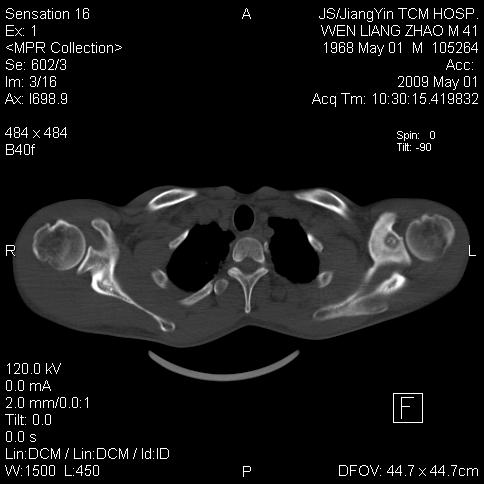

标题: CT19762:左侧喙突处压痛二年。考虑骨样骨瘤。

左侧喙突处压痛二年。考虑骨样骨瘤。

考虑骨样骨瘤,骨母细胞瘤待排。

病灶外缘膨胀明显,灶缘硬化较少,结合病史较符合骨母细胞瘤,其他亦不排除如软骨及软骨母细胞瘤等(病灶形态,成份较符合,发病部位也符合,只是年龄较大),骨样骨瘤多有较明显的自发性痛,且夜间痛明显,病史为压痛两年,不太符合.

多考虑内生性软骨瘤。年龄及发病部位及病史不支持骨样骨瘤。

支持骨样骨瘤(瘤巢小于1.5mm),骨母细胞瘤又称为巨大骨样骨瘤指瘤巢大于2cm的骨样骨瘤.

首先考虑内生软骨瘤,其次才考虑骨样骨瘤。